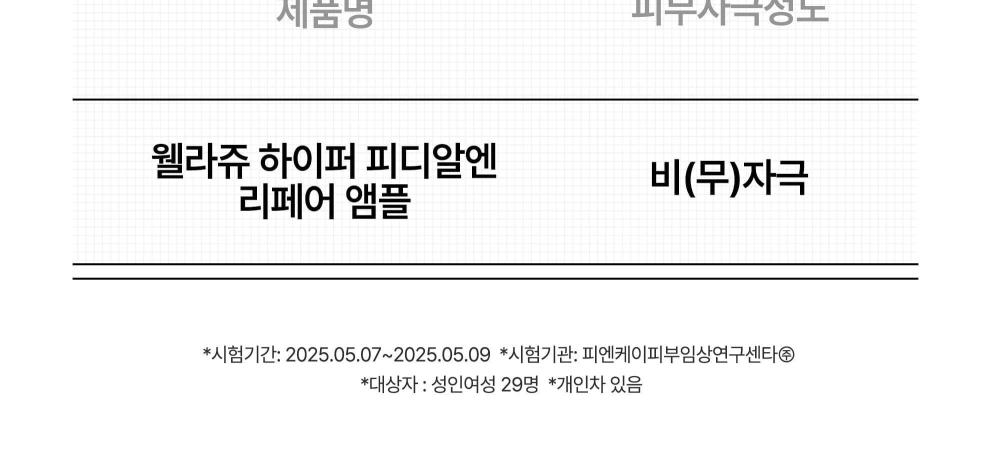

- 「皮膚 plumping(豐盈)效果之人體適用試驗」。

- 物理性刺激造成受損肌膚的即時(暫時)內在屏障改善」。

- 表層屏障薄弱或受損的敏感肌